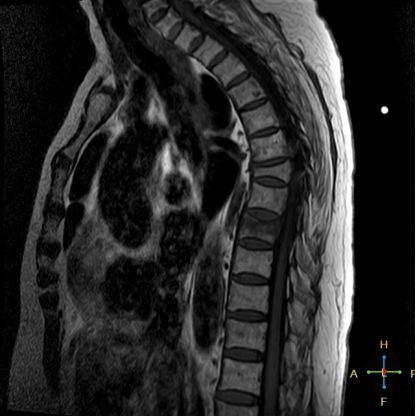

——良性压缩性骨折MR信号特点—— 良性骨折的修复过程:缺血性变化--修复(骨髓水肿、血流增加或充血现象)--修复近完成(血流恢复正常)--慢性期(脂肪组织再生)。 正常成人:椎体为黄骨髓,T1WI 、T2WI 均为高信号。 当骨髓内出现水肿时,T1 低信号, 与残余的正常骨髓形成明显对比,所以椎体压缩骨折后,MR 信号改变以 T1WI 上观察最好;而在常规 T2WI 图像上,病变骨髓的长 T2 高信号与正常骨髓脂肪信号差别较小,不易观察;T2WI 脂肪抑制技术对于突出显示骨折区长 T2 组织信号具有独特优势,对于判断椎体是否发生脂肪变及骨折是否愈合也有一定价值。 急性早期,椎体压缩,局部缺血,骨髓水肿,T1WI 不均匀低信号,T2WI 高信号,增强扫描无明显的强化。 随后,骨折部位开始修复,血流量增加,增强扫描可出现明显的强化,平扫信号无改变。 慢性期,骨髓内脂肪组织再生,T1WI 椎体内呈混杂高信号。

由于大多数外力轻微,椎体内多形成范围局限、移位不明显的骨折线,骨折线周围水肿亦多局限,因此,较少出现全椎体信号异常。

椎体后角回避现象:T1WI 椎体上部或大部呈低信号, 而后角信号不变。

椎弓根改变:由于旋转的扭力或是上下的压力造成椎体血流循环改变而致椎弓根的髓内水肿,使信号改变累及椎弓根,但椎弓根无变形或膨大。

所以,椎弓根的信号改变并非恶性骨肿瘤所特有,约20%~ 30%的良性压缩性骨折会出现椎弓根水肿而信号增高。 恶性压缩性骨折, 约有60%~ 80%出现椎弓根水肿及信号变化,而在椎弓根出现不正常信号的恶性压缩性骨折中, 约有50%~70%出现椎弓根膨大的现象,为其特异性, 可作为鉴别诊断的依据。 椎旁软组织肿块:最典型的表现为椎旁一薄环状异常信号带,因为椎体压缩时常继发椎旁软组织水肿与出血, 这一征象多见于单纯骨折, 病理性骨折少见。